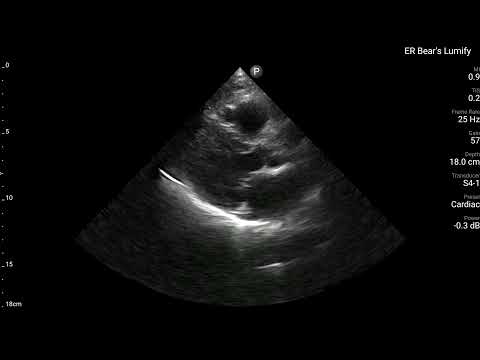

當時我用了自己Lumify做了Echo,大家會希望在哪個地方看出什麼問題呢?

所以我們在ECG看到懷疑是Post.wall MI,當然我們超音波的目光就要放到Post.wall的附近(Segment 4、5、10、11都要看),是否有明顯RWMA。如果有,那麼超音波的發現就和ECG的發現完全吻合,就更可證明這確實就是Post.wall MI。

看Fig.5左側,可以知道A4C其實不容易看到Post.wall。A2C與PSAX可以看到。

- PSAX是看縱切面,可以看到Segment 4、5、10、11

PSAX是最佳可以看到Post.wall與其附近RWMA的最好view。

回頭看看上面的POCUS Clip(PSAX view),把一根手指頭放在LV中間,有沒有發現Segment 4、5附近是不是不太動。

賓果!!!!

POCUS finding is compatible with ECG finding.

Tips:如果懷疑Post.wall MI →PSAX view就最好eyeballing觀看的view